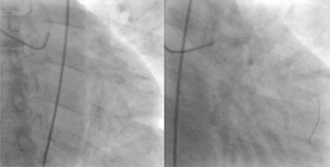

![]() A coronary angiogram showing the circulation in the left coronary artery and its branches. | |